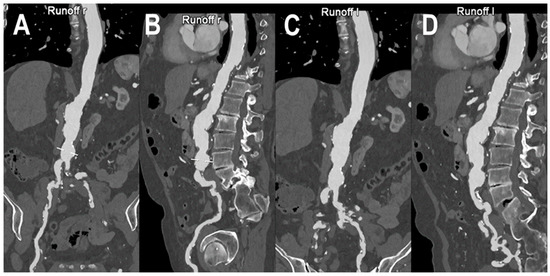

- Euler, A.; Higashigaito, K.; Mergen, V.; Sartoretti, T.; Zanini, B.; Schmidt, B.; Flohr, T.G.; Ulzheimer, S.; Eberhard, M.; Alkadhi, H. High-Pitch Photon-Counting Detector Computed Tomography Angiography of the Aorta: Intraindividual Comparison to Energy-Integrating Detector Computed Tomography at Equal Radiation Dose. Investig. Radiol. 2022, 57, 115–121. [Google Scholar] [CrossRef]

- Higashigaito, K.; Mergen, V.; Eberhard, M.; Jungblut, L.; Hebeisen, M.; Rätzer, S.; Zanini, B.; Kobe, A.; Martini, K.; Euler, A.; et al. CT Angiography of the Aorta Using Photon-counting Detector CT with Reduced Contrast Media Volume. Radiol. Cardiothorac. Imaging 2023, 5, e220140. [Google Scholar] [CrossRef] [PubMed]

| Higashigaito et al. [48] | 2022 | In vivo (human) | 39 | Aorta | PCCT with reconstructions of VMI at 40, 50, and 60 keV showed a significantly increased CNR at similar image quality compared to EID-CT at identical radiation dose. |

| Euler et al. [49] | 2022 | In vivo (human) | 40 | Aorta | Compared with EID-CT at matched radiation dose, PCCT angiography of the aorta with VMI at 40 and 45 keV resulted in a significant increase of CNR. The CNR gain was higher in overweight patients. |

| Higashigaito et al. [50] | 2023 | In vivo (human) | 100 | Aorta | Angiography of the aorta with PCCT was associated with higher CNR compared to conventional CT. PCCT with a low-volume contrast media protocol gave comparable image quality to that of EID-CT at the same radiation dose. |